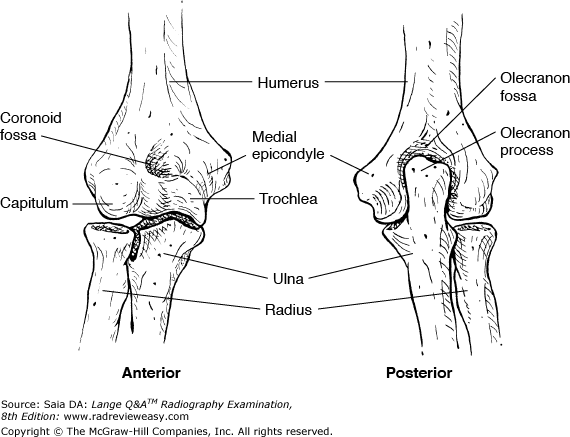

Which of the following projections/positions would best demonstrate structure number 6 seen in Figure 7–7?

A PA projection

B Lateral projection

C AP external oblique

D AP internal oblique

-The figure shows a posterior view of the elbow. The distal posterior humerus (number 1) is seen, as well as the proximal posterior radius (number 4) and ulna (number 3). Additional structures identified are the medial epicondyle (number 2), the olecranon fossa (number 5), olecranon process (number 6), lateral epicondyle (number 7), and radial head (number 8) The olecranon process (number 6) can best be demonstrated in the lateral projection; it can also be demonstrated in the acute flexion position. The AP internal oblique will demonstrate the coronoid process; the AP external oblique will demonstrate the radial head free of superimposition.

Which of the following is (are) located on the distal aspect of the humerus?

1.Capitulum

2.Intertubercular groove

3.Coronoid fossa

A 1 only

B 1 and 2 only

C 1 and 3 only

D 1, 2, and 3

-The distal humerus articulates with the radius and ulna to form the elbow joint. The lateral aspect of the distal humerus presents a raised, smooth, rounded surface, the capitulum, that articulates with the superior surface of the radial head. The trochlea is on the medial aspect of the distal humerus and articulates with the semilunar notch of the ulna. Just proximal to the capitulum and the trochlea are the lateral and medial epicondyles; the medial is more prominent and palpable. The coronoid fossa is found on the anterior distal humerus and functions to accommodate the coronoid process with the elbow in flexion. The intertubercular (bicipital) groove is located on the proximal humerus.